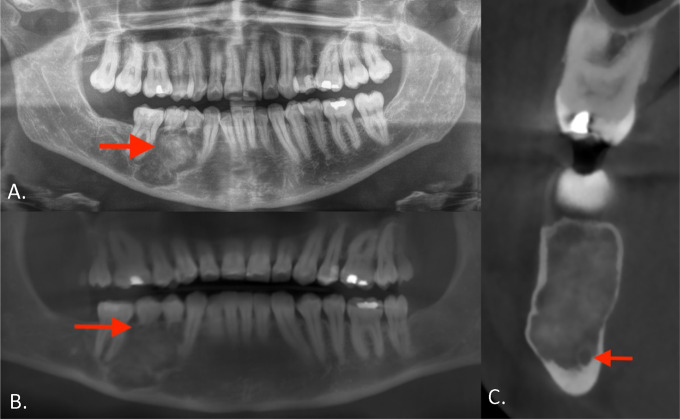

教学点:骨水泥骨化纤维瘤是颌骨的一种良性肿瘤,具有混合透光-不透光外观,引起牙根吸收和骨扩张。

Teaching point: Cemento‑ossifying fibroma is a benign tumor of the jaws with a mixed radiolucent-radiopaque appearance and causes root resorption and bone expansion.